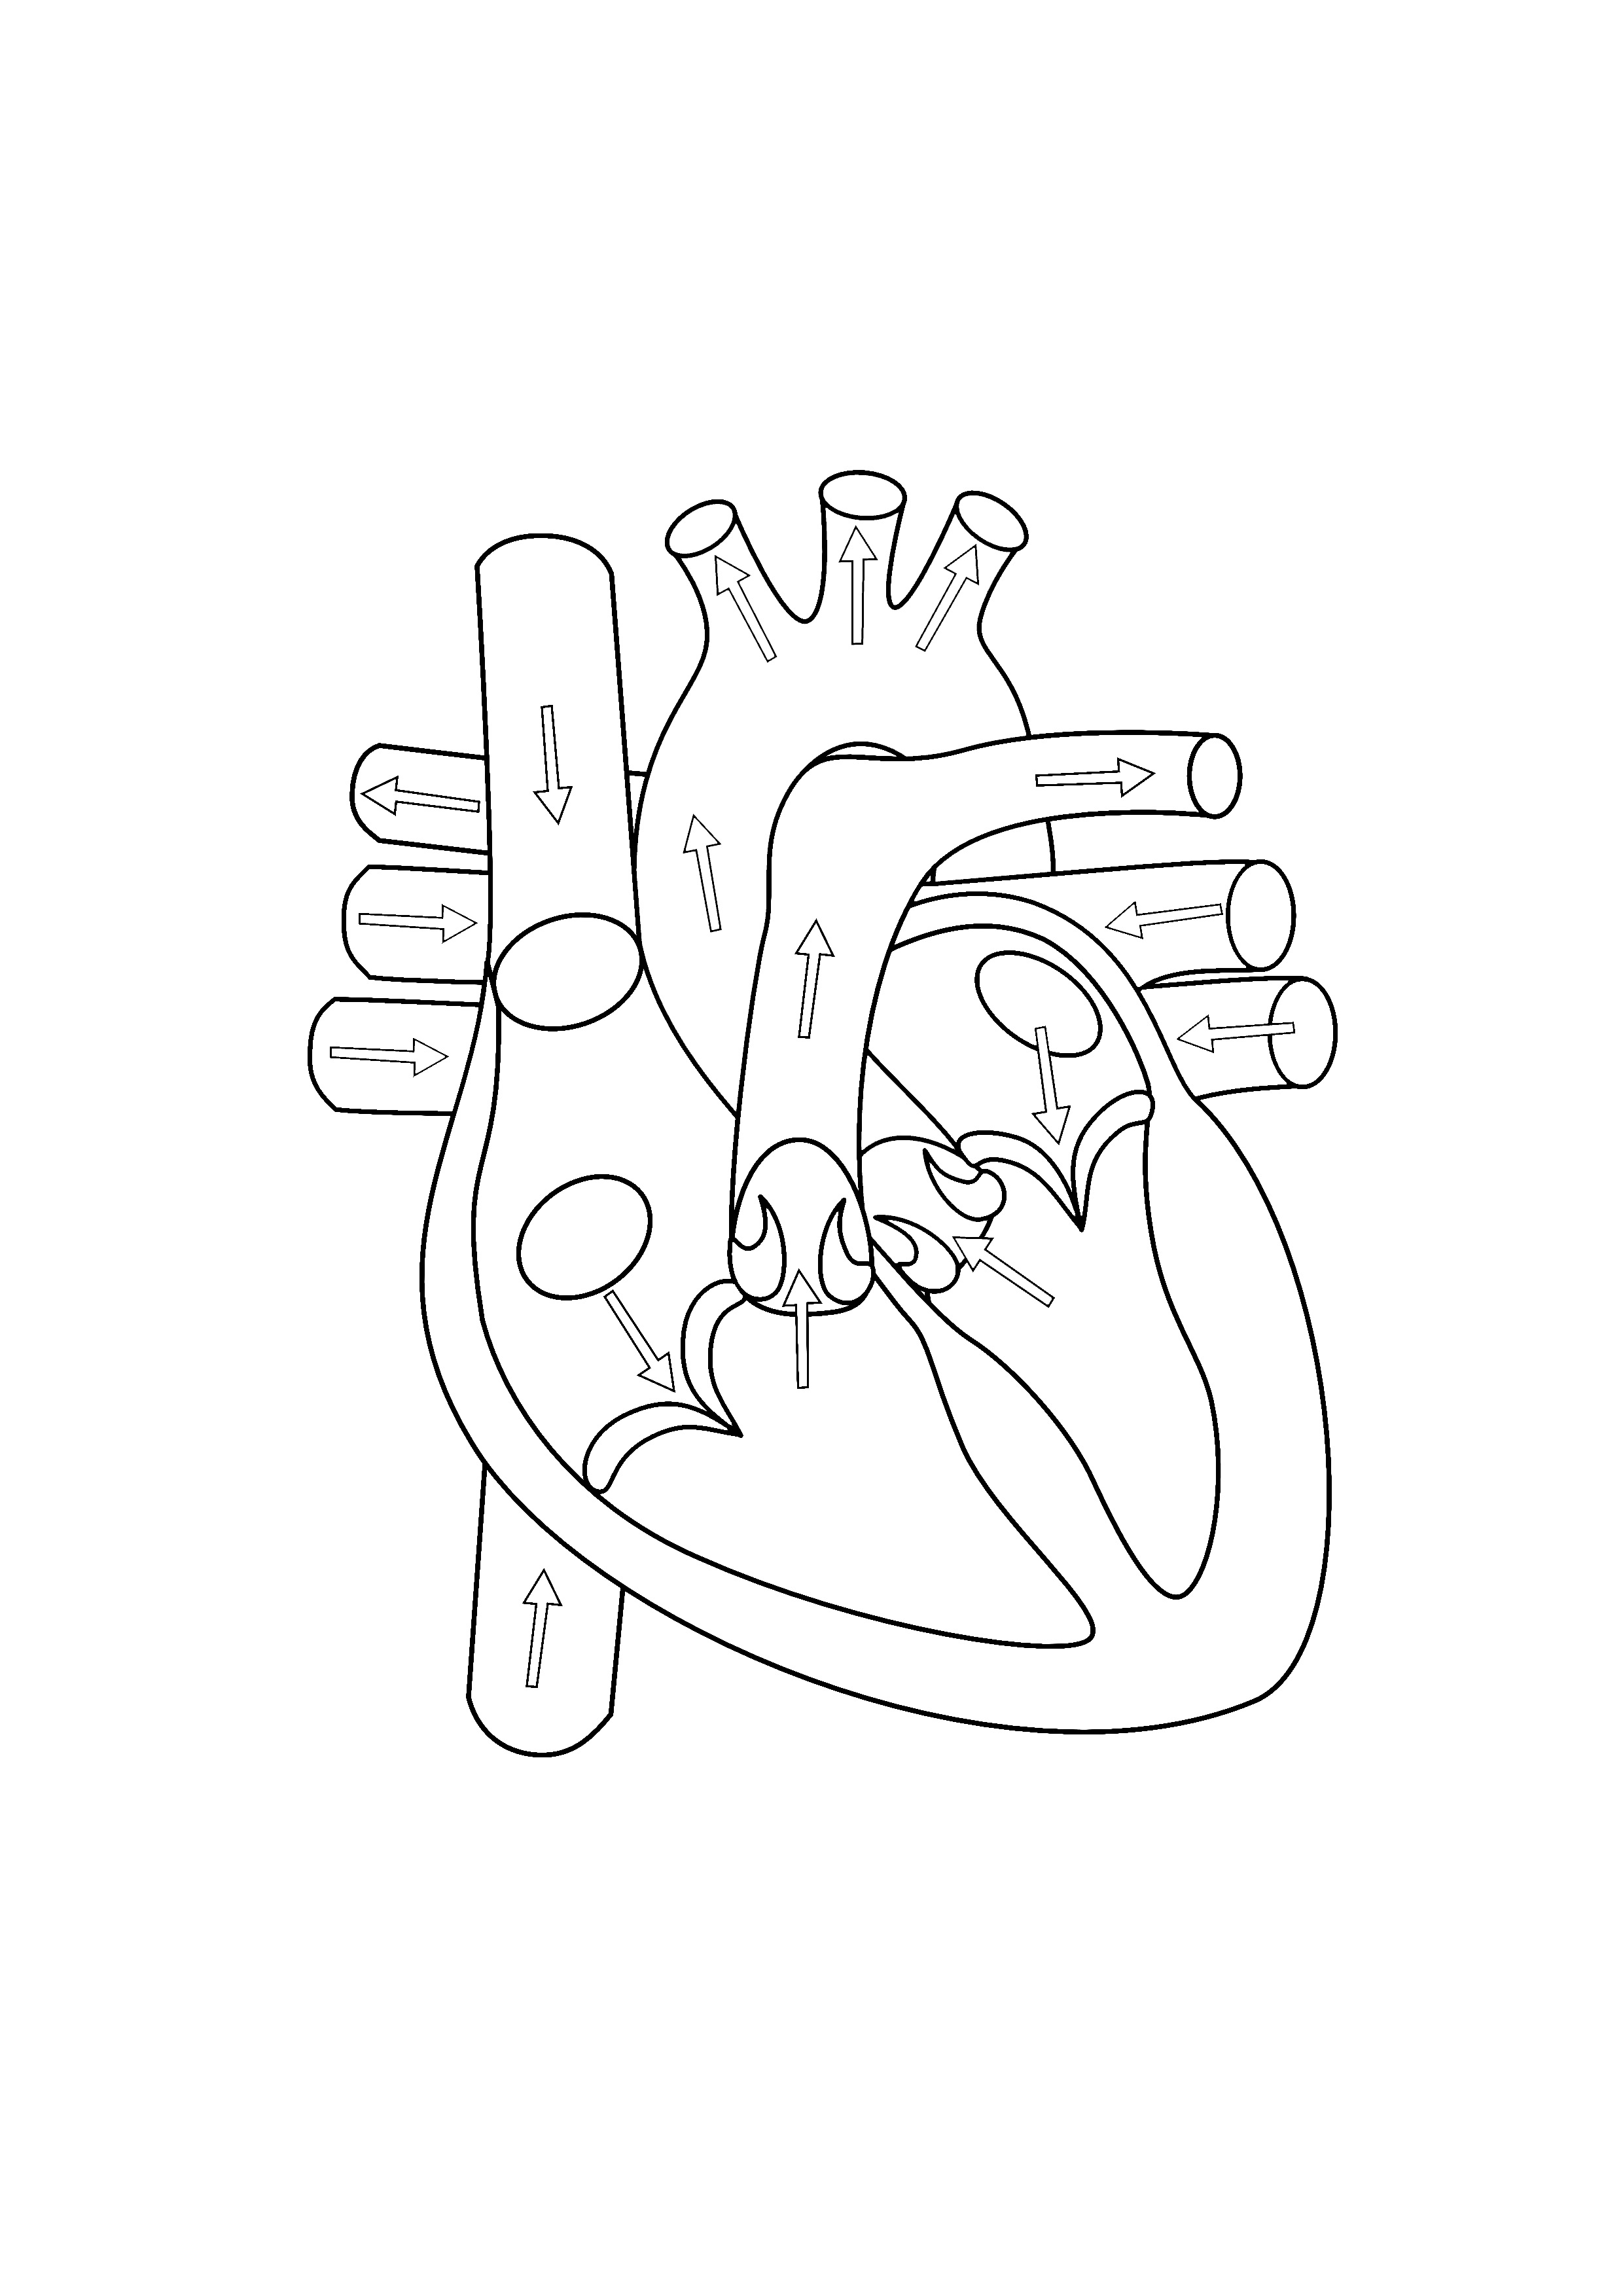

2480x3508 Simple Human Heart Diagram Drawing Human Heart Diagram Without